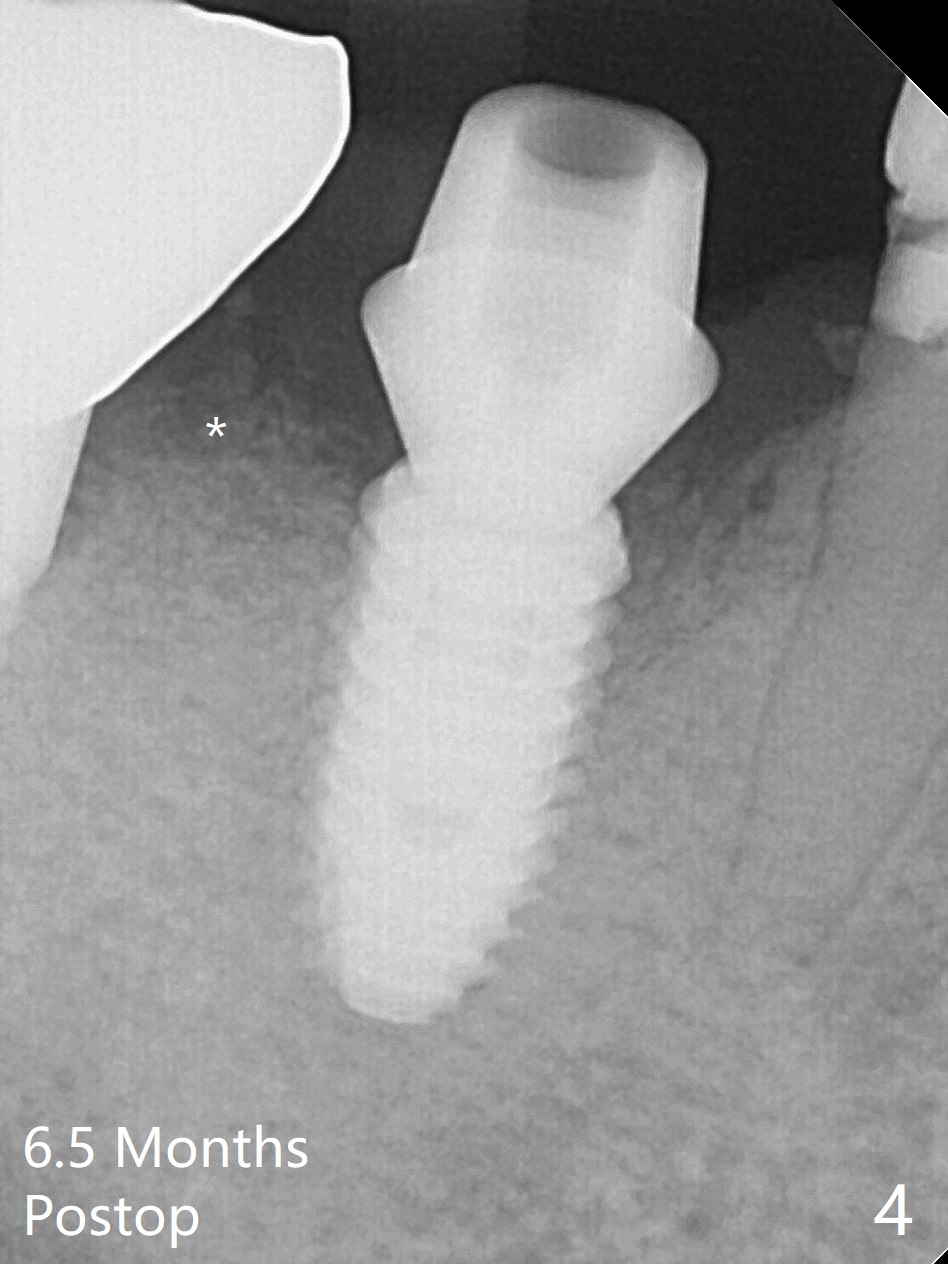

As compared to guided delayed implant placement, the immediate one in the 1st molar needs one more Lidocaine and one Septocaine for pain control. Trajectory is as good as expected with >50 Ncm (Fig.1,2 (red dashed line: superior border of the Inferior Alveolar Canal)). With insertion of Vanilla allograft with autogenous bone (Fig.1 *) and a 6.5x4(3) mm cementation abutment, an immediate provisional (Fig.3 P) is fabricated to keep the graft in place.